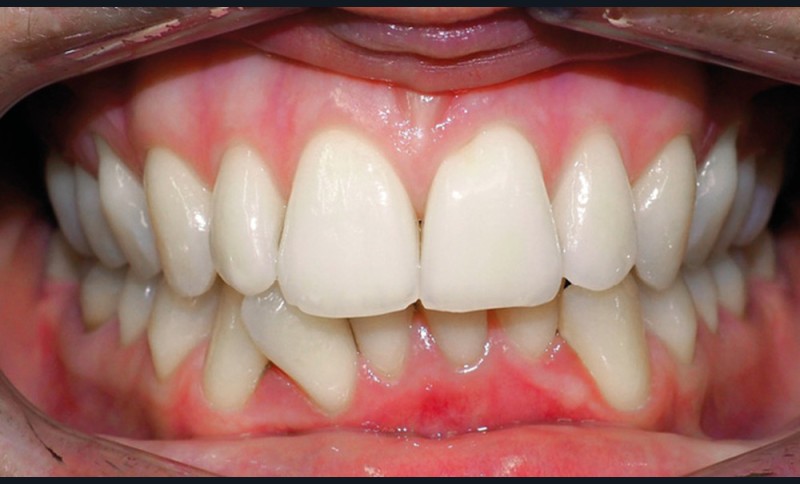

Examen endo-buccal (fig. 2a-e)

L’arcade maxillaire est parabolique, la 12 présente une légère mésio-rotation. L’arcade mandibulaire est également parabolique avec un encombrement antérieur estimé à 6 mm. On note une dyschromie de la 31, dont le test de vitalité est négatif. Le parodonte est fin.

En occlusion, on note une relation de Classe I molaire bilatérale avec un surplomb normal et une supraclusion. Les médianes incisives sont concordantes.

Les incisives maxillaires sont de forme triangulaire [1] et l’indice de Bolton est de 97 % qui traduit la présence d’une DDD par excès mandibulaire.

Discussion (fig. 4 à 7)

La durée du traitement a été de vingt-trois mois. Des mouvements lents ont permis un contrôle des axes incisifs mandibulaires.

Des triangles noirs sont apparus à la mandibule suite à l’extraction de 31 : ils ne sont pas exposés lors du sourire, ce qui n’entraîne pas de défaut esthétique.